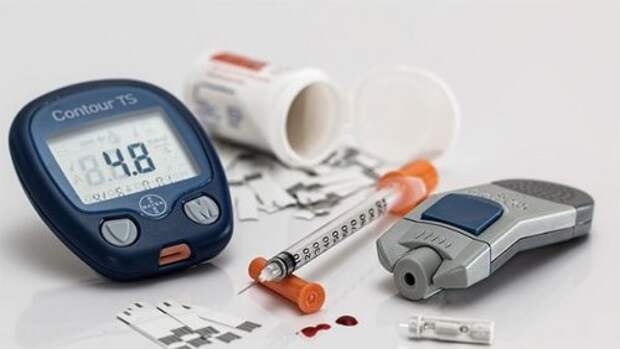

7. Первый тип диабета невозможно предотвратить полностью, но его развитие можно контролировать с помощью строгой диеты и постоянных проверок уровня сахара в крови.

7. Первый тип диабета невозможно предотвратить полностью, но его развитие можно контролировать с помощью строгой диеты и постоянных проверок уровня сахара в крови.